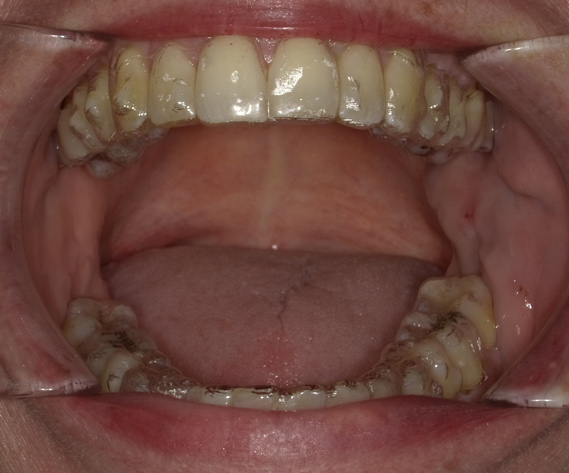

Fig 8. The appliance worn during treatment, anterior view (Fig 8), right side view (Fig 9), left side view (Fig 10), and upper arch view (Fig 11).

Figure 8

Intraoral scans were taken to document the patient's entire palate and bite registration. Scans were sent to the clinical team for the fabrication of a clear aligner/sleep appliance for the patient to wear; the chosen appliance fits over clear aligners, regardless of the tray number the patient may need (Figure 7 through Figure 11).

After the appliance was delivered, additional photographs were taken with the camera to ensure that the appliance was delivered as intended, to document the case, and to show the patient the ideal fit of the appliance in his mouth as instructions were reviewed with him.